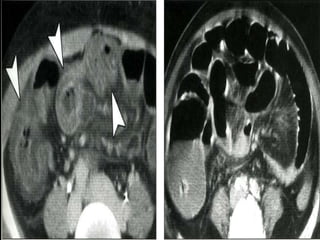

ROLE OF MRI

 Current role of MRI is yet to be defined.

 True FISP images is used to assess large

mesenteric vessel occlusion

 MRI has significant problem in detecting

small thromboemboli in peripheral vessels

 Routine use of MRI patients with suspected

mesenteric arterial occlusion may not be

justified

Sagittal subvolume and coronal subvolume MIP images show severe stenosis of

the celiac, superior mesenteric and inferior mesenteric arteries.